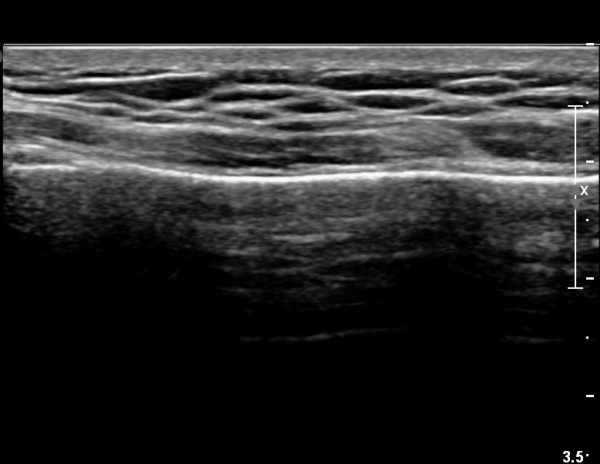

ÃÊÀ½ÆÄ °Ë»ç : ¼Õ¸ñ ¼ö±Ù°ü ±ÙÀ§ºÎ Ⱦ´Ü¸é°Ë»ç¿¡¼­ Äá¾Ë»À Ç¥ÃþÀ¸·Î ¾à°£ÀÇ ¿¬ºÎÁ¶Á÷ ºÎÁ¾ÀÌ °üÂûµÊ(»çÁø 1).